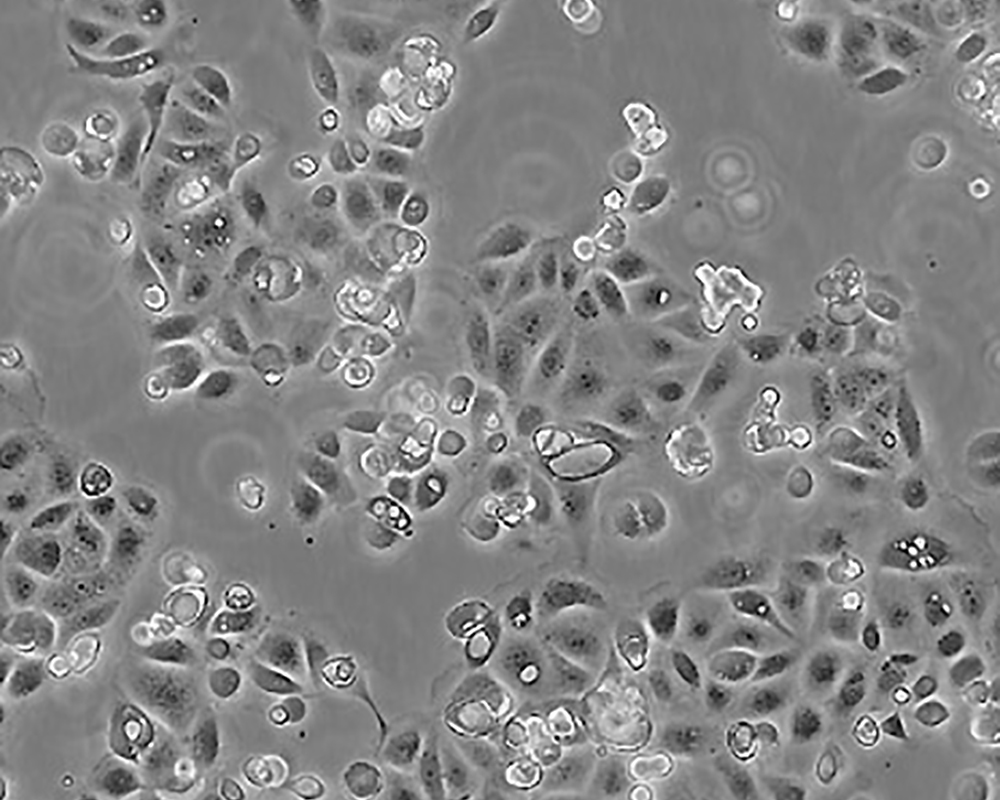

產品名稱 SW 1990

中文名稱 人胰腺癌細胞

生長特性 adhere

形態特征 epithelial

細胞描述 1978年從胰腺外分泌腺的胰腺腺癌II期患者的脾轉移灶中建立了SW 1990細胞株。 報道該細胞的植板率為29%。